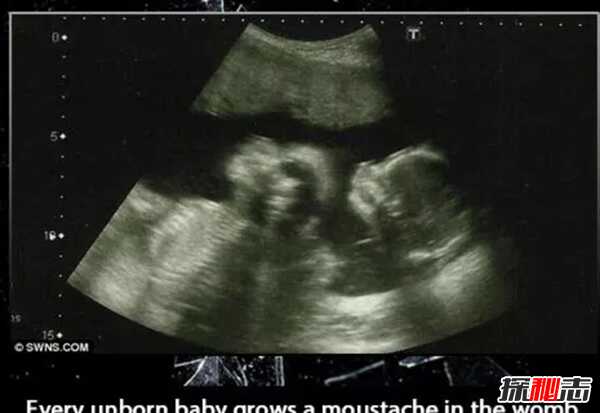

1、一个吃肉的人一生中平均要吃掉7000只动物,每个未出生的婴儿在子宫里都会长胡子。